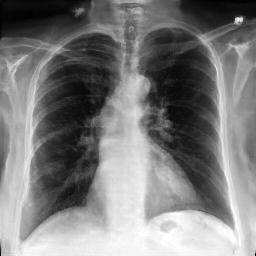

Image Reconstruction. Table 1 shows that the co-training scheme outperforms the \mathcal{E}-training approach in reconstruction accuracy, as indicated by higher PSNR and IW_SSIM scores, highlighting the benefits of joint optimization for enhancing reconstruction quality. The results are further validated by the visual comparison in Fig. 2, where the co-training scheme recovers input images with finer details and higher fidelity. In contrast, the \mathcal{E}-training scheme exhibits noticeable discrepancies when compared to the original images.

Refer to caption

XRX_{R}

Co-training

\mathcal{E}-training

Fig. 2: Reconstruction results. The first row displays the real images XRX_{R}. The last two rows show the reconstructed images X^R\hat{X}_{R} produced by the proposed co-training scheme and the \mathcal{E}-training scheme, respectively.